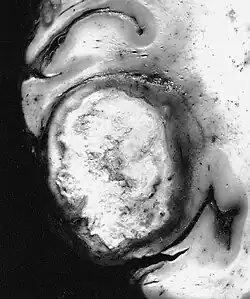

Das Riesenzellglioblastom ist eine Variante des Glioblastomes. Zusammen mit dem Gliosarkom und dem Epitheloidem Glioblastom wird es als IDH-Wildtyp bezeichnet und in der WHO-Klassifikation der Tumoren des zentralen Nervensystems als Grad IV eingestuft. Kennzeichnend sind ausgeprägte mehrkernige (mehr als 20 Kerne) Tumorriesenzellen bis zu 400 µm Durchmesser.